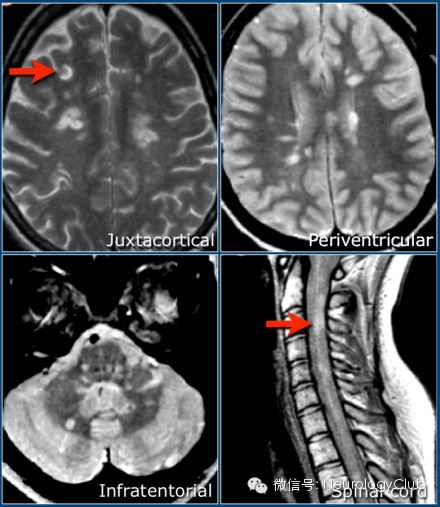

第一方面:T2像上的脑室旁病灶

1T2像脑室旁多发高信号,为紧贴脑室表面的不对称性分界清晰的病灶

2、脑室旁病灶的长轴与侧脑室方向垂直,线样或椭圆样

3、其与白质纤维束的辐射性及脑室周围静脉方向一致

第四方面:皮质下白质病变

1、通常累及U形纤维

2、缺血性疾病以脑皮质为基底的楔形分布不累及U形纤维,可与鉴别